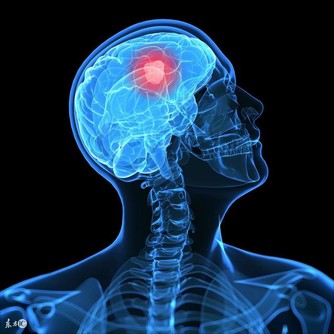

心絞痛的發作有兩種形式,一種是典型發作,這種非常好鑑別,發作的位置是在心前區,並且有壓榨憋悶的感覺,在舌下含服硝酸甘油之後,就能夠得到明顯的緩解,這就是很典型的心絞痛。但是心絞痛有很多時候發作起來並不典型,有的時候,發作的部位是在胃脘部,有的時候僅僅是左側肩臂疼痛,這些疼痛只是一過性的,這就很難鑑別。

當然診斷心絞痛還需要結合以往的病史,一般如果一個人長時間的高血脂高血壓,心血管事件發生率本來就比較高的情況下,發生上述表現就應該及時去醫院查心電圖,有的時候心電圖並不能及時捕捉到心臟的疾病,可以做一個24小時動態的心電圖,同時檢查一下心肌酶等心臟疾病相關指標,做到早發現,早診斷,早治療。